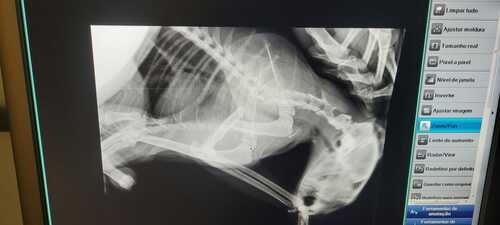

A Chica foi raptada de nossa casa, e quando a encontramos descobrimos que foi atropelada 2x. A sua patinha está quebrada e precisará ser amputada. Com o HVET da UnB conseguimos um bom desconto, carinho e atenção com a nossa Chiquinha.

(IMAGENS DA FRATURA)